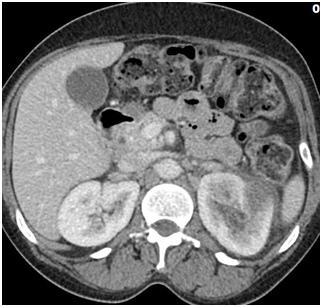

After approximately 48 hours of admission, the patient’s symptoms improved, she became afebrile and her white cell count returned to normal range. IV ceftriaxone was stopped and switched to oral ciprofloxacin. Repeat CT scan of the abdomen and pelvis after 48 hours of presentation showed that the previously noted 2 cm hypodense area in the upper pole of right kidney had become more circumscribed with decrease in density consistent with focal pyelonephritis. No fluid collection was noted (Figure 4). The patient had an uneventful recovery and was discharged home on oral ciprofloxacin to complete a total duration of 21 days. Patient was lost to follow up and a repeat imaging of the kidney could not be obtained.

Figure 4 Computed tomographic scan of abdomen and pelvis with intravenous contrast of case 2 , forty-eight hours after admission showing no change in more focal 2 cm area in the upper pole of the right kidney, which most likely represents focal pyelonephritis .( Acute lobar nephronia).